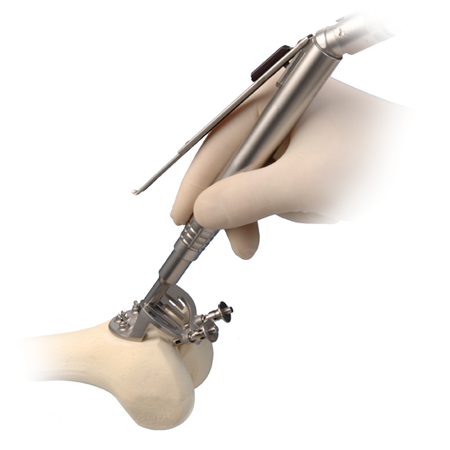

その他 PLACEBO NAVIGATE SYSTEM JOINT Gender Solutions® Patello-Femoral Joint System | Zimmer Biometの詳細情報

Gender Solutions® Patello-Femoral Joint System | Zimmer Biomet。40160-AX00B Ball Joint Nissan March/Tiida/Note K12/C11/Z11。Biamp NMS-NG10GPX-AVB。ストレス解消法を学べるDVD。Upadacitinib for the treatment of active non-radiographic。- タイトル: PLACEBO NAVIGATE SYSTEM JOINT- ジャンル: 健康・フィットネス- 発行者: 山内要- 内容: ストレス解消法、体の調整法- 言語: 日本語- フォーマット: DVD波動カード付いてますご覧いただきありがとうございます。※新品ケース交換済み ジャイアントロボ DVD 全4巻セット。